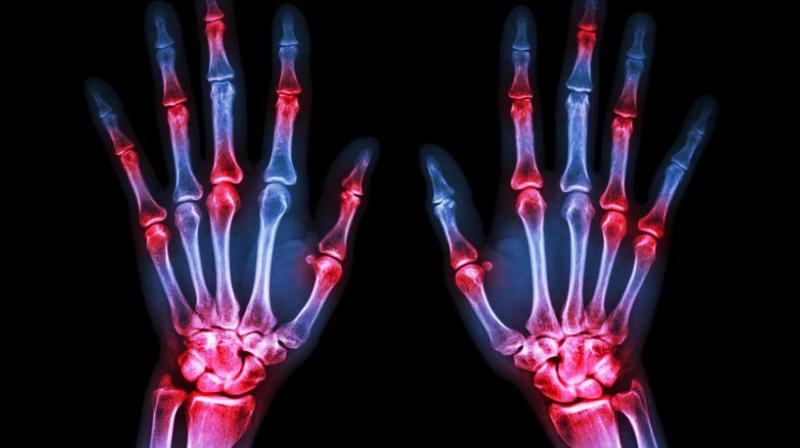

ਵਰਤਮਾਨ ਸਮੇਂ ਵਿਚ ਯੂਰਿਕ ਐਸਿਡ ਬਨਣ ਦੇ ਮਾਮਲੇ ਬਹੁਤ ਤੇਜ਼ੀ ਨਾਲ ਵੱਧ ਰਹੇ ਹਨ। ਇਹ ਆਧੁਨਿਕ ਜੀਵਨ ਸ਼ੈਲੀ ਦਾ ਇਕ ਗੰਭੀਰ ਰੋਗ ਹੈ। ਸਰੀਰ ਵਿਚ ਪੁਰੀਨਸ ਦੇ ਟੁੱਟਣ ਨਾਲ ਯੂਰਿਕ ਐਸਿਡ ਬਣਦਾ ਹੈ। ਪੁਰੀਨਸ ਇਕ ਅਜਿਹਾ ਪਦਾਰਥ ਹੈ ਜੋਂ ਖਾਣ ਵਾਲੀਆਂ ਚੀਜ਼ਾਂ ਵਿਚ ਪਾਇਆ ਜਾਂਦਾ ਹੈ। ਖਾਣ ਵਾਲੀਆਂ ਚੀਜ਼ਾਂ ਨਾਲ ਇਹ ਸਰੀਰ ਵਿਚ ਪੁਜਦਾ ਹੈ ਅਤੇ ਫਿਰ ਬੱਲਡ ਦੇ ਮਾਧਿਅਮ ਨਾਲ ਵਹਿੰਦਾ ਹੋਇਆ ਕਿਡਨੀ ਤੱਕ ਪੁੱਜਦਾ ਹੈ। ਉਂਜ ਤਾਂ ਯੂਰਿਕ ਐਸਿਡ ਪਿਸ਼ਾਬ ਦੇ ਮਾਧਿਅਮ ਨਾਲ ਸਰੀਰ ਵਿਚੋਂ ਬਾਹਰ ਨਿਕਲ ਜਾਂਦਾ ਹੈ ਪਰ ਕਈ ਵਾਰੀ ਇਹ ਸਰੀਰ ਵਿਚ ਹੀ ਰਹਿ ਜਾਂਦਾ ਹੈ।

ਇਸ ਦੇ ਕਾਰਨ ਇਸ ਦੀ ਮਾਤਰਾ ਵਧਣ ਲੱਗਦੀ ਹੈ। ਜੇਕਰ ਸਮੇਂ ਰਹਿੰਦੇ ਇਸ ਦਾ ਇਲਾਜ ਨਾ ਕੀਤਾ ਜਾਵੇ ਤਾਂ ਵਿਅਕਤੀ ਲਈ ਇਹ ਨੁਕਸਾਨਦਾਇਕ ਹੋ ਸਕਦਾ ਹੈ। ਪੈਰਾਂ ਅਤੇ ਜੋੜਾਂ ਵਿਚ ਦਰਦ, ਅੱਡੀਆਂ ਵਿਚ ਦਰਦ, ਜ਼ਿਆਦਾ ਦੇਰ ਬੈਠਣ ਉਤੇ ਜਾਂ ਉੱਠਣ ਵਿਚ ਪੈਰਾਂ ਅੱਡੀਆਂ ਵਿਚ ਅਸਹਿਣਯੋਗ ਦਰਦ, ਸ਼ੂਗਰ ਦਾ ਪੱਧਰ ਵੱਧਣਾ। ਅੱਜ ਅਸੀ ਤੁਹਾਨੂੰ ਸਰੀਰ ਵਿਚ ਯੂਰਿਕ ਐਸਿਡ ਵਧਣ ਦੇ ਲੱਛਣ ਅਤੇ ਇਸ ਦੇ ਘਰੇਲੂ ਉਪਾਅ ਦੱਸਾਂਗੇ।